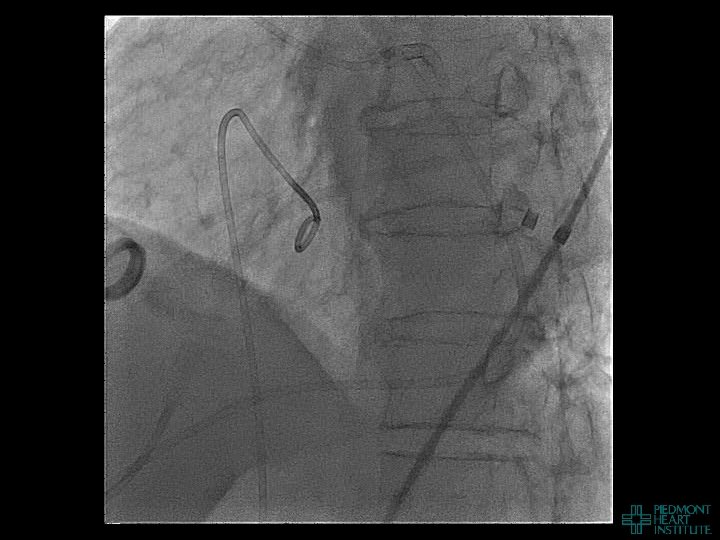

Coronary Perforation Methods of Patient Management • Dual Catheter (‘Ping Pong’) Technique • Prolonged

Coronary Perforation Methods of Patient Management • Dual Catheter (‘Ping Pong’) Technique • Prolonged balloon inflation and covered stents • Reversal of anticoagulation — Know contradictions to protamine sulfate for UFH; Avoid bivalirudin, LMWH — Reserve GP 2 b 3 a inhibition until successful crossing and wire change-out Embolization • — Coil, gelfoam, methacrylate, autologous blood/fat • Microcatheter Occlusion • Confirmation of successful management — Contralateral injection — Right heart catheterization — Echocardiogram — Contrast echocardiography